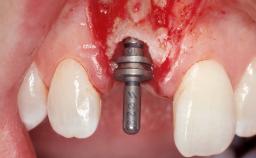

Immediate Placement of an Implant in a Maxillary Left Central Incisor Site

A 33-year-old female patient presented with an upper left central incisor that required extraction after a failed endodontic therapy. The tooth had been traumatized when the patient was a teenager and had undergone several endodontic treatments, including two apicectomy procedures. The patient was in good health and did not smoke. Clinical examination showed that the patient had a high lip line. In full smile, the gingival margins of the upper teeth were visible to the first molars. The gingival margins of central incisors 11 and 21 were only just showing. Examination of tooth 21 confirmed that the tooth was mobile and had hypererupted by 1 mm.

Type of Implants One-Piece

Placement Protocol Immediate implant placement

Tooth Site Maxillary incisor or canine

Socket Morphology Single-root socket

Socket Integrity Damage to one or more bone walls

Bone Volume Damage to one or more socket walls